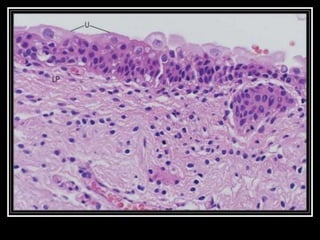

The urinary bladder develops during the 18th week of fetal development. It is located in the pelvic cavity behind the pubic symphysis in males and anterior to the uterus in females. The bladder has a muscular wall and receives its blood supply from branches of the internal iliac artery, including the superior and inferior vesical arteries. Nerve supply comes from pelvic splanchnic nerves via the hypogastric plexus and pudendal nerves. The bladder drains lymph into pelvic lymph nodes and is supported by ligaments attached to surrounding structures in the pelvis. Microscopically, it has a mucosa, submucosa, muscularis and adventitia layers.